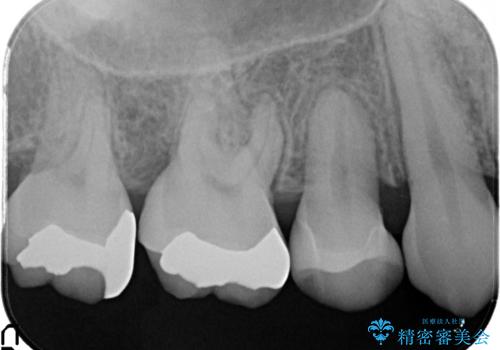

- 笑ったときに銀の詰め物が見えることを主訴に来院されました。

セラミックインレーにて修復を行いました。

保険治療で使える材料には制限があり、見た目だけでなく精度でも劣ります。当院でのセラミックインレーは歯とのつなぎ目を拡大鏡で確認して精度高く仕上げるため、むし歯のリスクを限りなく少なくできるよう治療します。